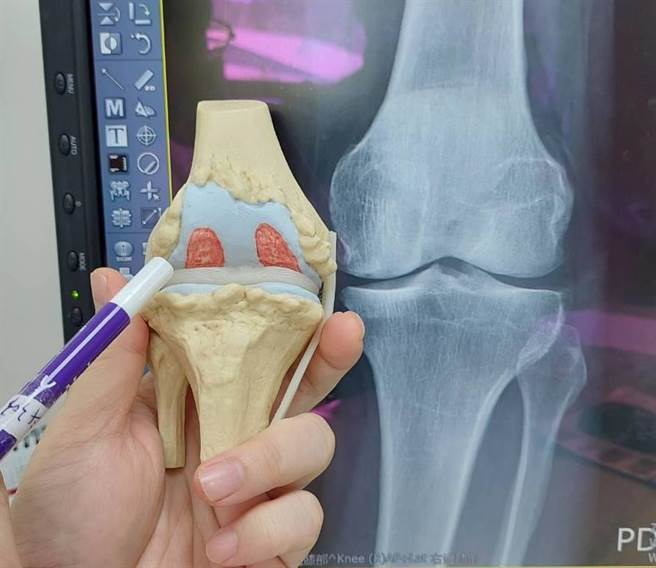

陈先生的膝关节磨损相当严重,导致双脚歪斜又疼痛。(大千医院提供/李京升苗栗传真)

腰椎的问题解决后,则由骨科继续接手治疗其膝盖退化的问题。罗浩儒医师表示,陈先生过去尝试过许多治疗方式,像是施打玻尿酸、PRP、甚至接受膝关节镜清理治疗,但都无法改善。

在详细检查之后,发现他的膝关节退化非常严重,导致走路时双脚歪斜、疼痛,因此建议以人工关节置换术治疗。术后第二天陈先生即可下床练习走路,之前的症状也获得良好的改善。